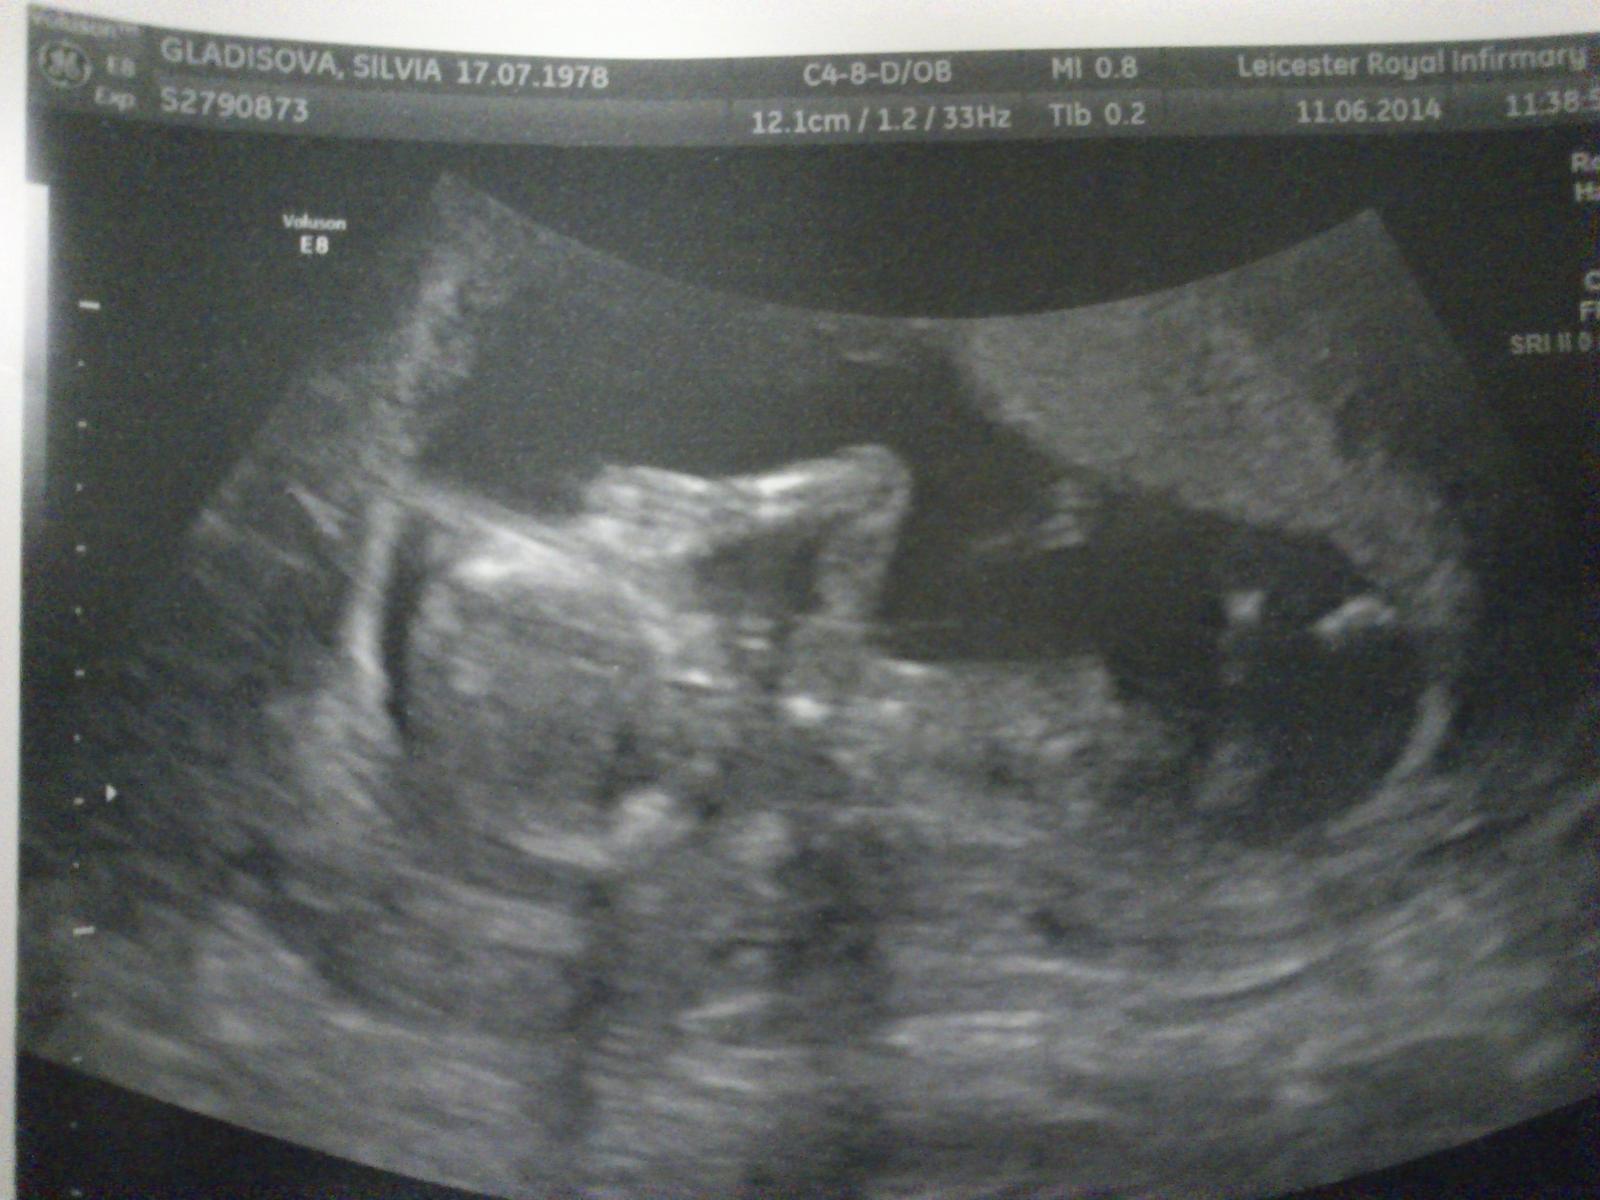

@point111 čaaau. No mám dostať v utorok. Som po tých hormónoch. Mala som tri fol.jeden dominantný. A od dnes ma bolia bradavky. V sobotu robím test. A ľavá strana kde boli vajíčka bolí stale teda cítim to. Tak som hrozne zvedavá. Teplotu mám 37,4 každým dnom vyššiu. Po ovu bola 38. Potom dám vedieť. Čo ty ako? Myslela som na teba. Pekne že píšes. Teším sa!